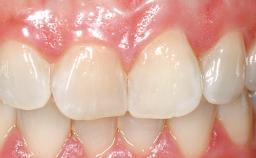

Late Flapless Placement of an Implant in a Maxillary Left Central Incisor Site

A 39-year-old male patient presented with a chief complaint of discomfort and gingival discoloration around his maxillary left central incisor. He was in good general health and was a non-smoker. His past dental history was significant because of the traumatic fracture of tooth 21 in a sporting accident at age 13. Initial dental treatment included endodontic therapy and a full-coverage restoration. The patient became symptomatic 5 years later, when structural failure of the tooth resulted in the dislodgment of the crown. Endodontic retreatment, apical surgery, and post-and-core restoration were performed.